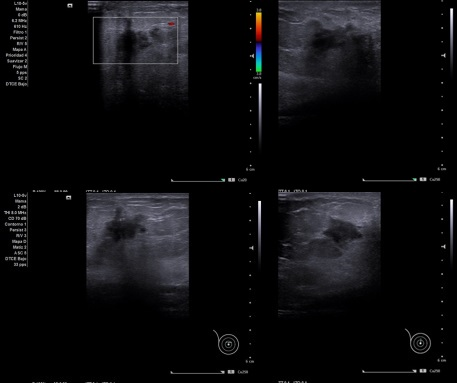

Caso 3: Mujer de 55 años que hace algunos días se observa bultoma en CSE de mama derecha, justo por encima del pezón. Sin antecedentes de importancia.

Caso 3: Lesión en zona superior central a la areola, ecoestructura de limites irregulares e hipoecogénica, microcalcificaciones de 12 x 12 aproximadamente, no captación de Doppler.

Caso 3: Biopsia + PAAF de radiodiagnóstico de adenopatía axilar derecha, hallazgos citológicos positivos para células neoplásicas, compatibles con una metástasis ganglionar de un carcinoma de probable origen mamario.

Caso 3: Adenocarcinoma mamario.

Diagnóstico diferencial: Tumoración benigna de mama.

Caso 3: quimioterapia neoadyuvante por 6 meses y luego intervención quirúrgica.

En el Caso 3 la paciente recibiendo quimioterapia y en el resto no ha sido requerido seguimiento.